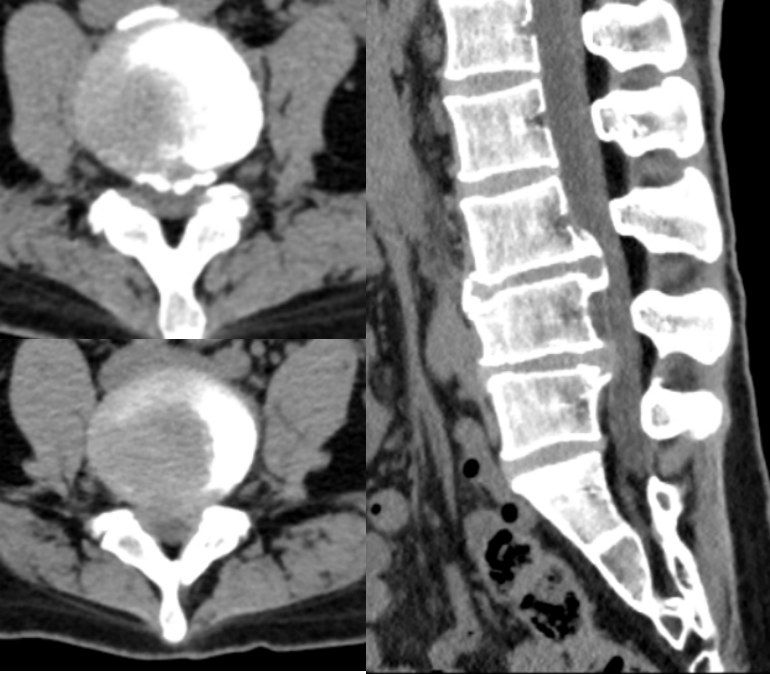

病例(减压不彻底,椎间盘残留)

男,73岁。

主诉:腰痛2年、加重伴右下肢疼痛麻木4个月,右足底、小腿后外侧为著。

术后右下肢症状无明显改善

思考和建议

减压区域应达到椎弓根中段,侧隐窝、椎间隙以及椎间孔内部3个区域都应充分减压